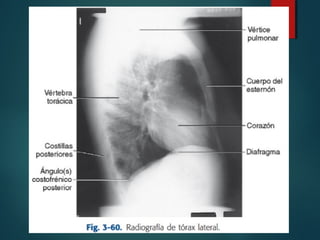

Lateral:

 Lateral izquierda

 Lateral derechas

 Visualiza zonas

ciegas como

espacio

retrocardiaco o

seno costofrénico

posterior.

RADIOGRAFÍA DE TORAX

RADIOGRAFÍA DE TORAX Lateral: Lateral izquierda  Lateral derechas  Visualiza zonas ciegas como espacio retrocardiaco o seno costofrénico posterior.